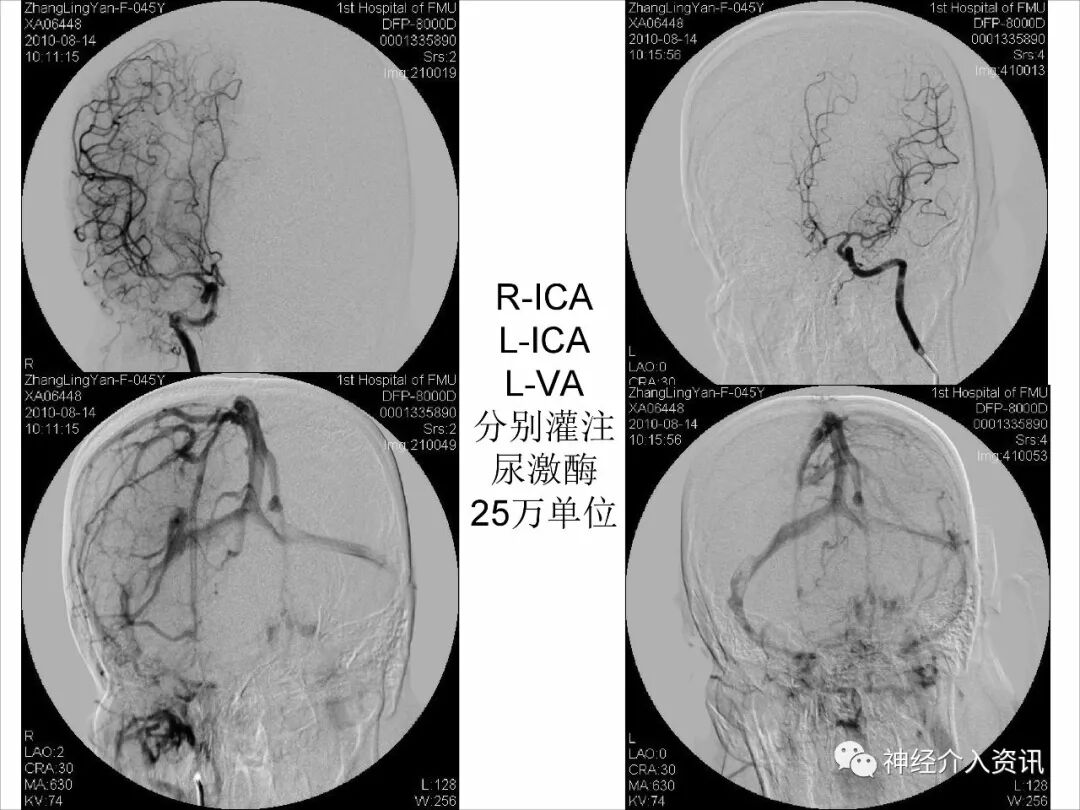

今天为大家分享的是由福建医科大学附属第一医院戴琳孙教授在第十二届华东地区脑血管病血管内治疗大会上带来的“脑静脉窦血栓的血管内治疗”精彩讲课视频和PPT,欢迎观看!(内容未经讲者审核,不当之处请与我们联系)